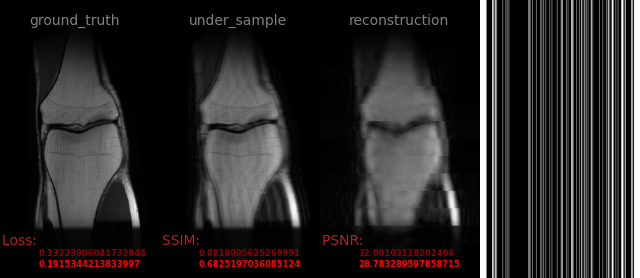

AVS-Net

Image-to-Image

medical

avs_b15_ndc